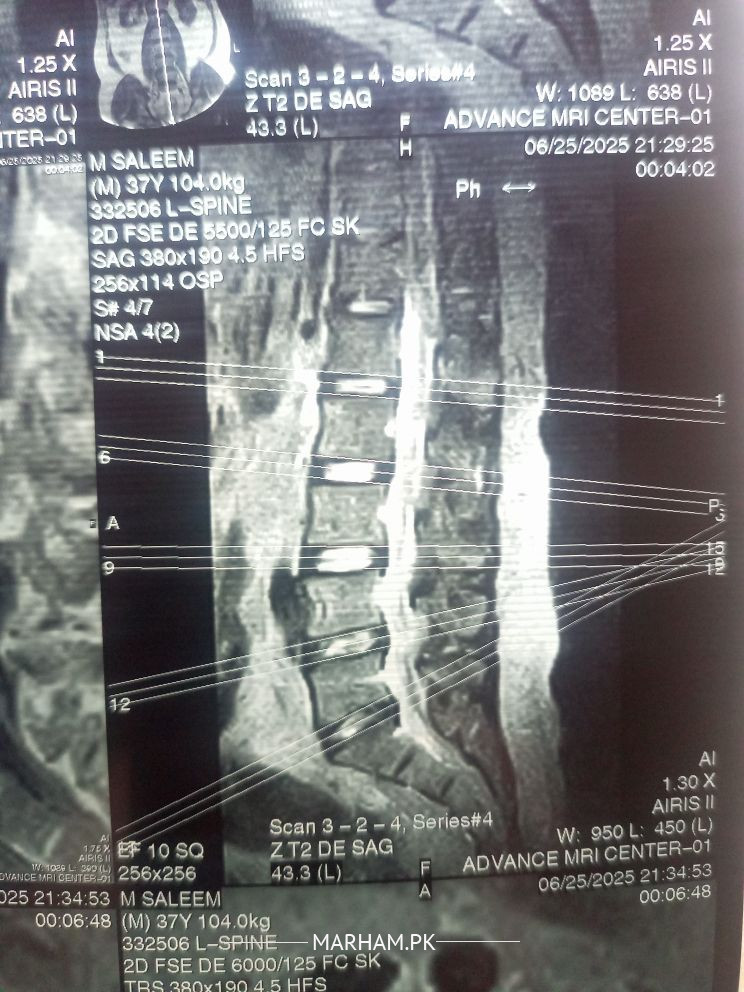

Physiotherapist in Lahore - Dr. Suleman Ashiq

your L4-L5 and L5-S1 discs are dehydrated, it can be due to some old cause, and L5-S1 is damaged more, may be due to improper lifting. so best solution is physiotherapy considering the complications of surgery, so yes physiotherapy will work if you give your therapist some time. good luck

It's not sciatica,It is disc dehydration at level L4-L5, but if you can share your MRI report that will be more helpful. yes physiotherapy will work for it but first visit a good orthopedic and then physiotherapis.